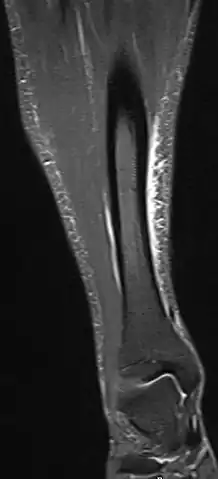

Red area represents the tibia. Pain is generally in the inner and lower 2/3rds of tibia.

A shin splint is pain along the inside edge of the shinbone (tibia) due to inflammation of tissue in the area.[1] Generally this is between the middle of the lower leg to the ankle.[2] The pain may be dull or sharp and is generally brought on by exercise.[1] It generally resolves during periods of rest.[3] Complications may include stress fractures.[2]

Shin splint pain is described as a recurring dull ache, sometimes becoming an intense pain, along the inner part of the lower two-thirds of the tibia.[4] The pain increases during exercise, and some individuals experience swelling in the pain area.[5] In contrast, stress fracture pain is localized to the fracture site.[6]